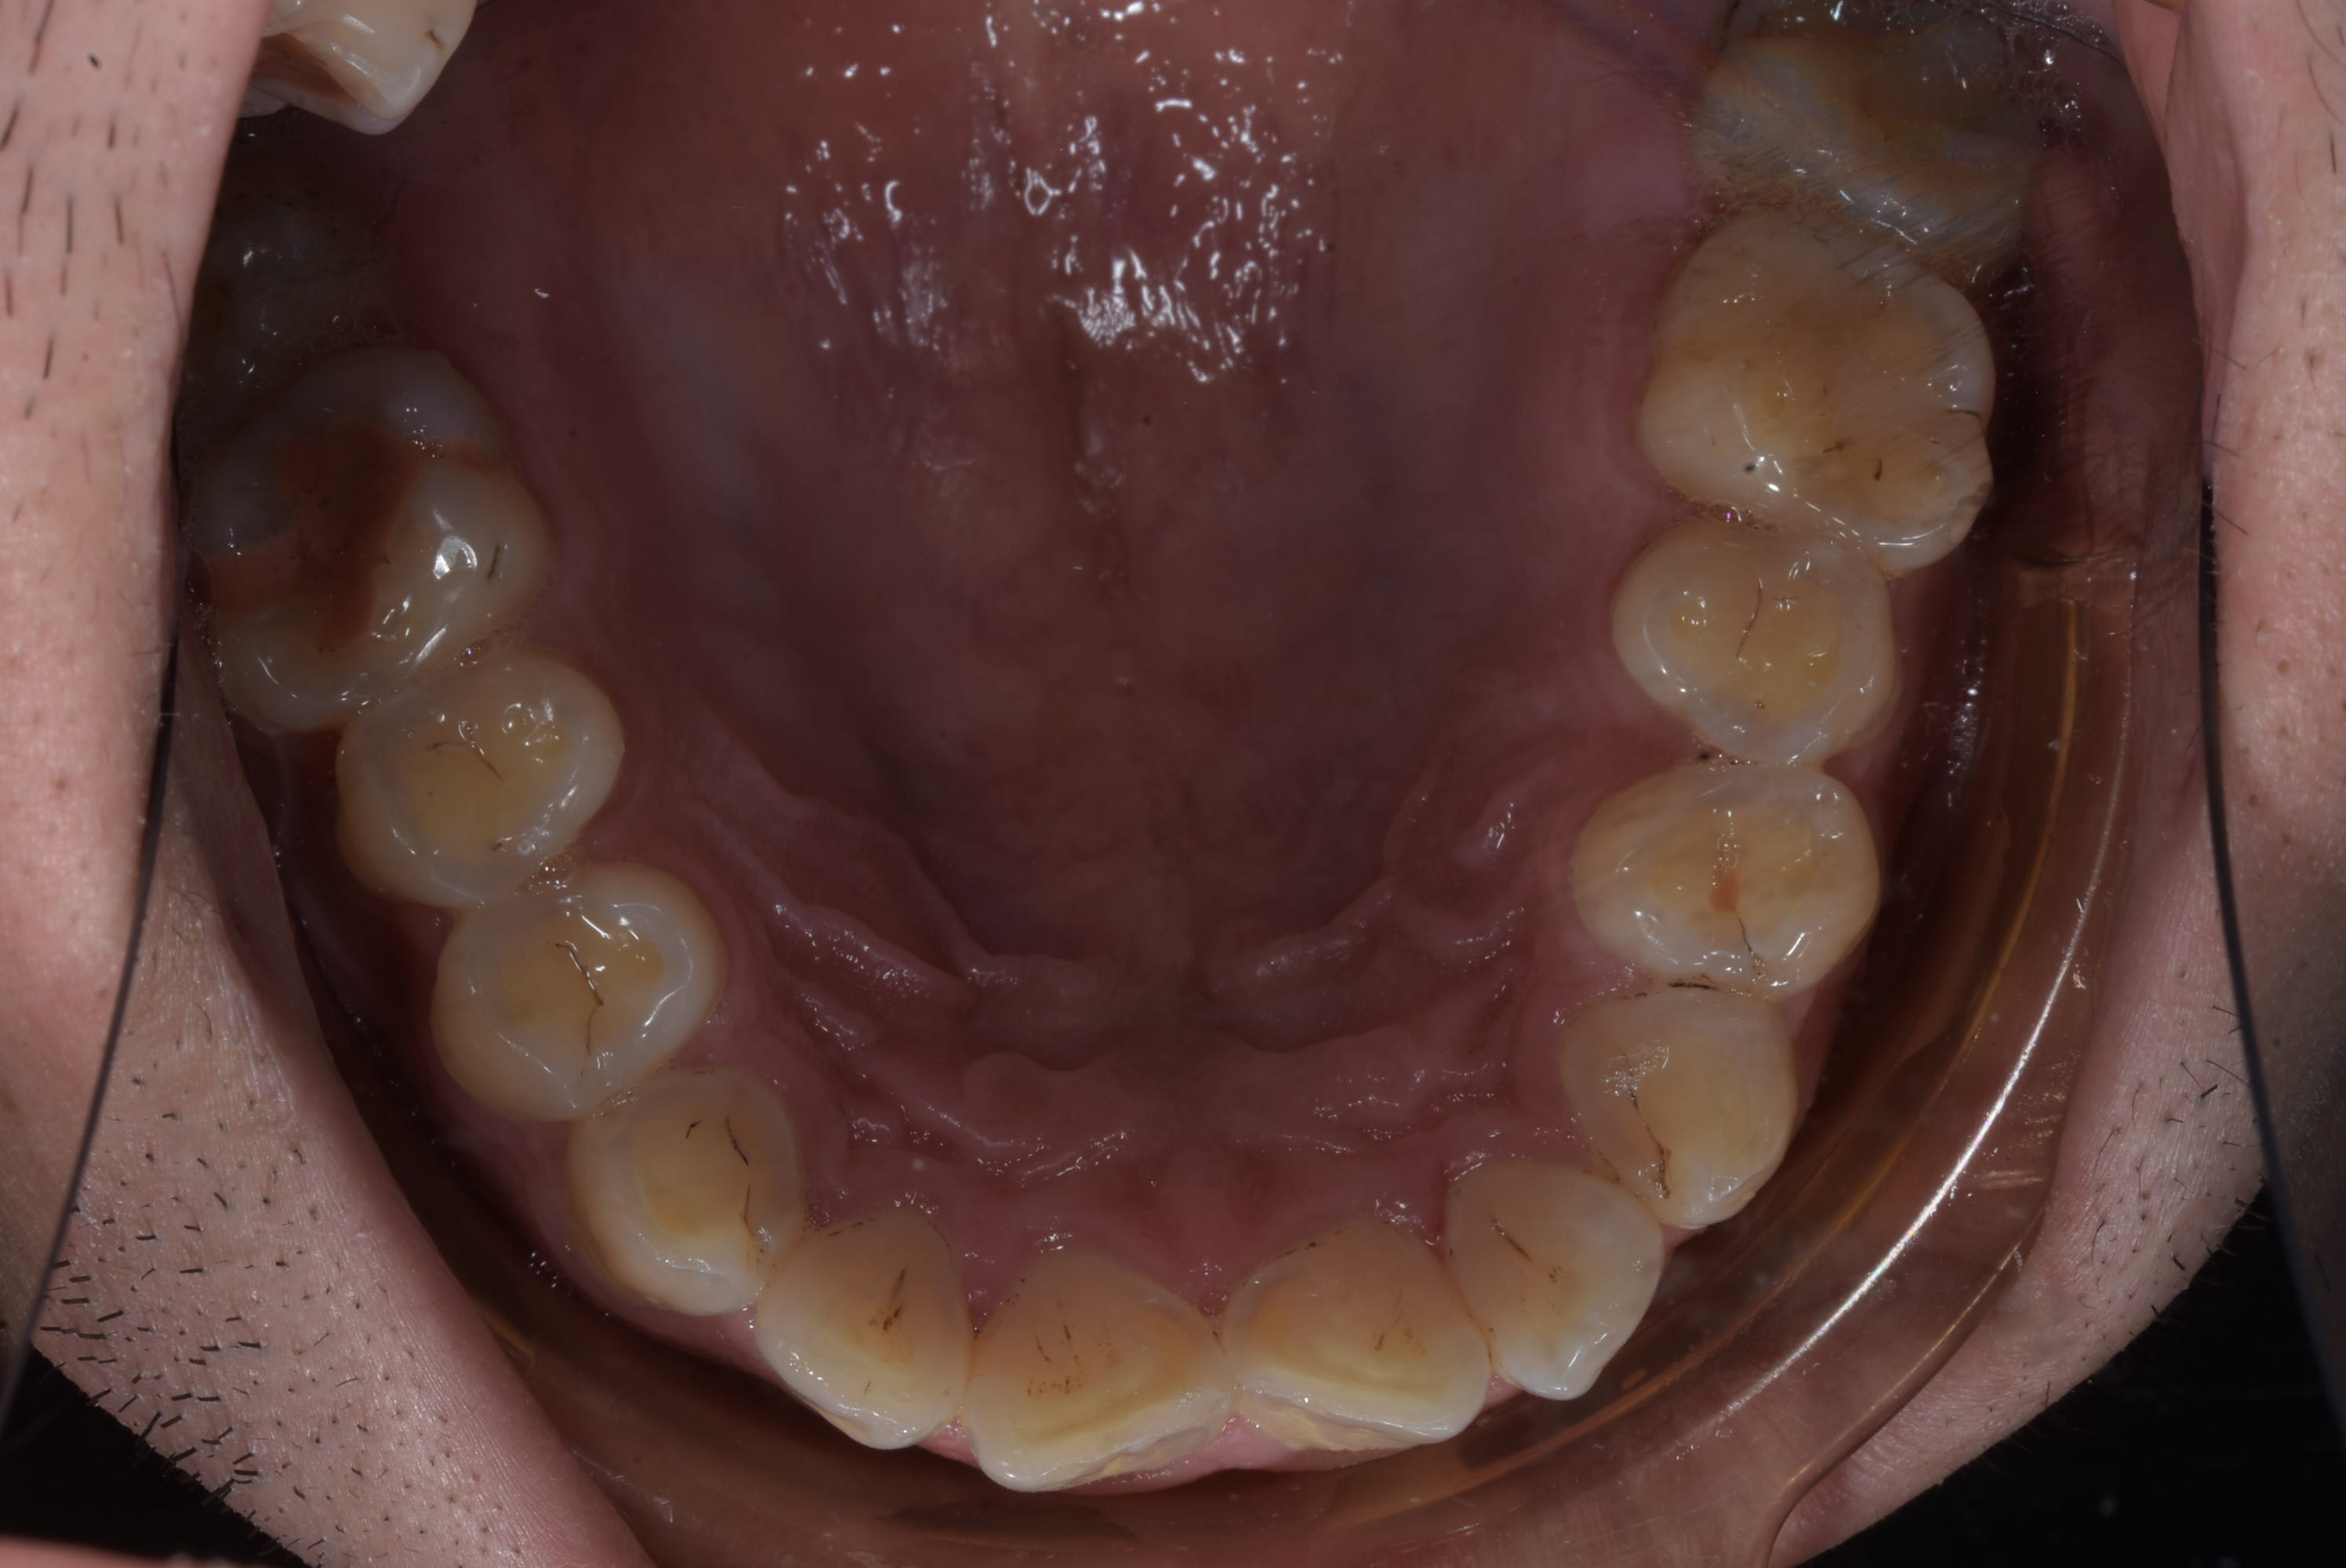

Ici le patient à besoin d'un traitement complet mais j'ai un soucie, la 46 est absente et la 47 versé et à une rotation.

J'ai un paquet de patient avec des 6 absente et des 7 versées , mettre un fil droit direct, surtout ici à cause de la rotation c'est t'exposer à un paquet de force parasite en gros :

- la molaire va vouloir s'egresser ( ici pas trop un soucie avec l'occlusion mais quand même à surveiller ) la j'ai put mettre direct un niti 18 et la semaine prochaine je devrais passer sur du niti 16 22 avec un set pour l'intrusion

J'ai mis le bracket en 45 en position apical et celui en 47 en position plus occlusal

- les prémo vont vouloir partir en lingual a cause de la rotation de la 7

- le bloc 3 a 5 va vouloir se verser en mésial

En aparté le patient aura plus que probablement un défaut paro sur la 47